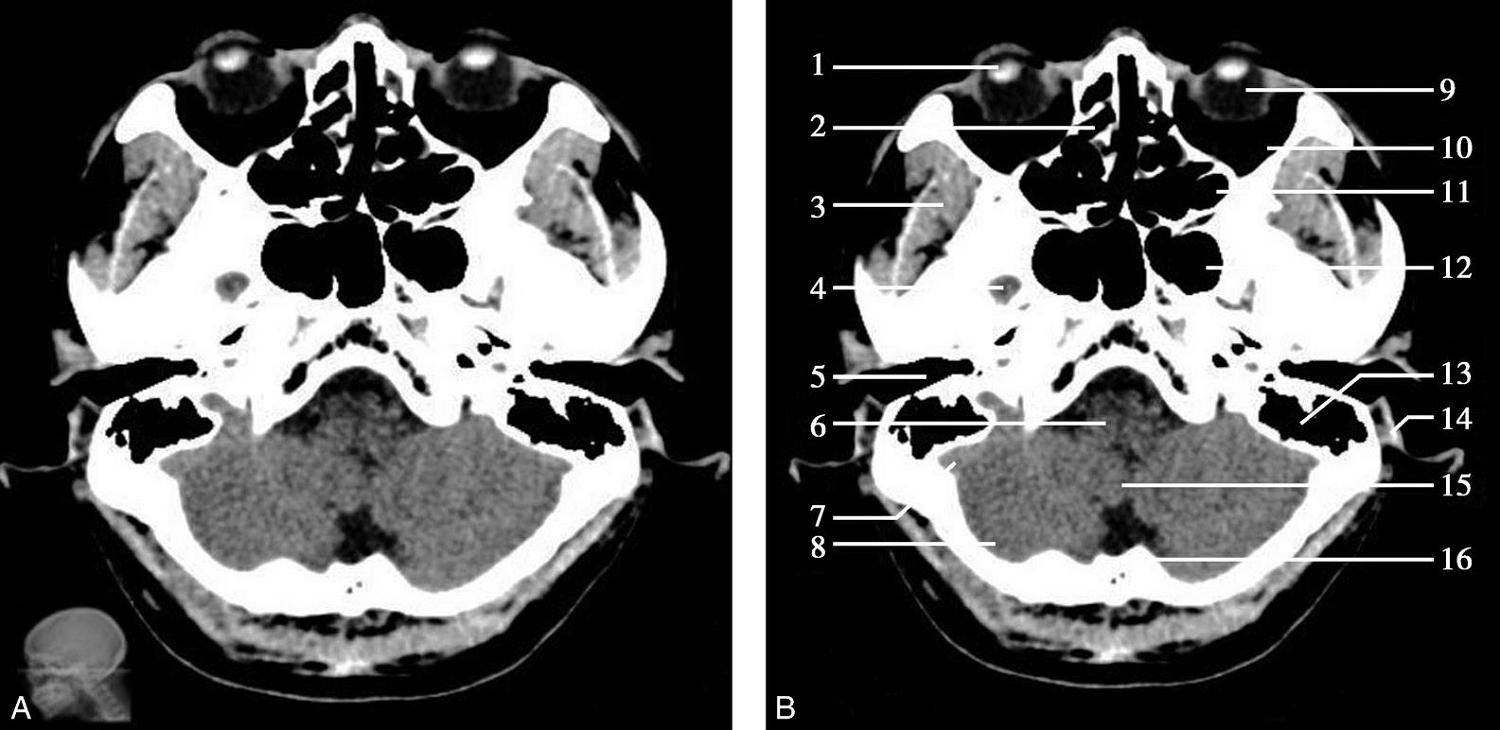

图1-2-2 颅底层面(骨窗)

A.横断面;B.横断面标注

1.鼻骨;2.筛窦纸板;3.颧骨眶突;4.翼腭窝;5.蝶骨大翼;6.卵圆孔;7.破裂孔;8.颞骨颧突;9.棘孔;10.斜坡;11.颞骨岩部;12.乳突;13.颈静脉孔;14.枕乳突缝;15.枕骨;16.枕内隆凸

层面前部呈开口向前的“V”字形,正中为鼻中隔,向两侧依次为筛窦和眼眶,眼眶内前部为眼球,后部为眶脂体。翼腭窝位于眼眶后部,窝内含有脂肪并有上颌神经通过。层面中部为蝶骨体,蝶骨体中部可见含气蝶窦,蝶窦后方为枕骨基底部,两者呈前后关系,其上面构成斜坡。蝶窦两侧为蝶骨大翼,其后外侧缘处由前向后可见卵圆孔和棘孔,分别有下颌神经和脑膜中动脉通过。斜坡外侧、岩骨尖前方为破裂孔。蝶骨大翼与眶外侧壁的颧骨借颧弓相连,颧弓和蝶骨大翼之间有咬肌及颞肌。层面中部外侧为外耳道。颞骨岩部呈“八”字形,相互之间借破裂孔软骨、蝶岩软骨结合和岩枕软骨结合连接。岩部后外侧的乳突部内可见乳突小房,乳突部与枕骨相接。岩骨后部可见颈静脉孔,内有颈内静脉、舌咽神经、迷走神经和副神经通过。层面后部为颅后窝,其内可见延髓,延髓前方为延髓前池,内有椎动脉,后外侧为小脑半球下部,后方为第四脑室、小脑扁桃体及小脑蚓部。